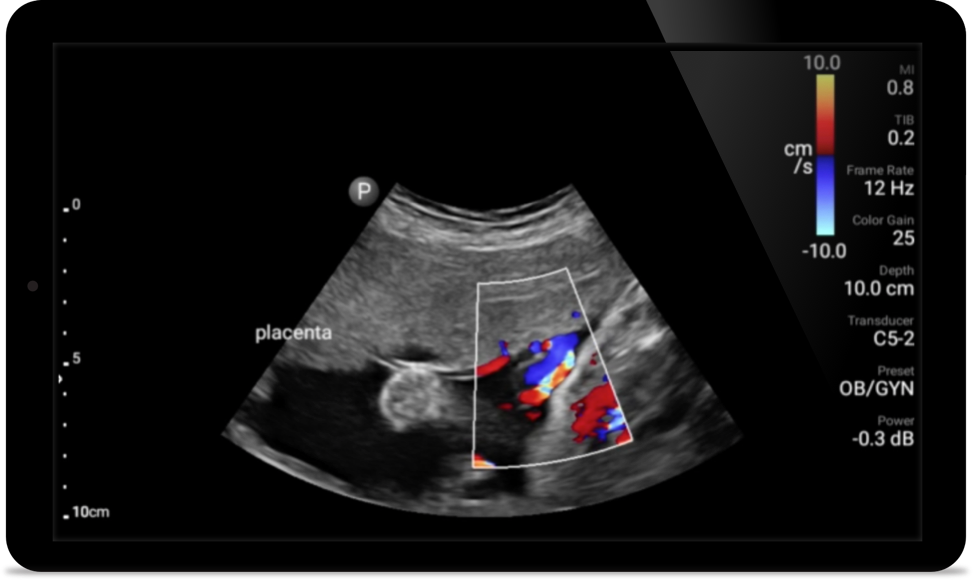

• Rango extendido de frecuencias de operación entre 12 y 4 MHz • Tamaño de apertura: 34 mm • 2D, Doppler orientable a color, Modalidad M, XRES avanzado e imágenes armónicas multivariables, SonoCT • Imágenes de alta resolución para aplicaciones superficiales: tejidos blandos, vasculares, superficiales, musculoesqueléticos y pulmonares • Marcador de línea central • Transductor USB-C con cable reemplazable